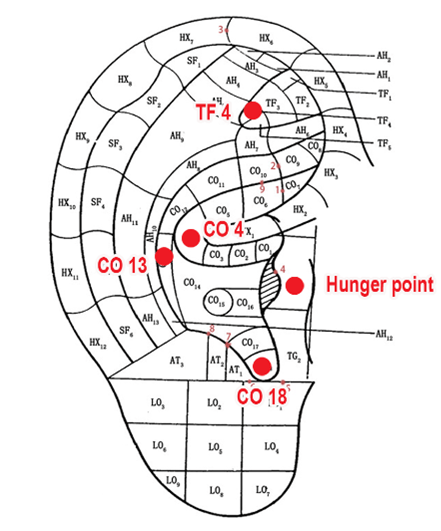

درمان AA: طب سوزنی گوش بهصورت هفتگی برای ۸ هفته با استفاده از چسبهای مربعشکل با طول ضلع ۱۰ میلیمتر همراه با سوزنهای ۰.۲۵ × ۱.۳ میلیمتری انجام شد. ۵ نقطه طب سوزنی در یک گوش شامل شنمن (TF4)، معده (CO4)، طحال (CO13)، غدد درونریز (CO18) و نقطه گرسنگی انتخاب شدند. نقاط طب سوزنی بر اساس استانداردهای فدراسیون جهانی طب سوزنی تعیین شدند. هر هفته گوش مورد درمان تغییر میکرد.